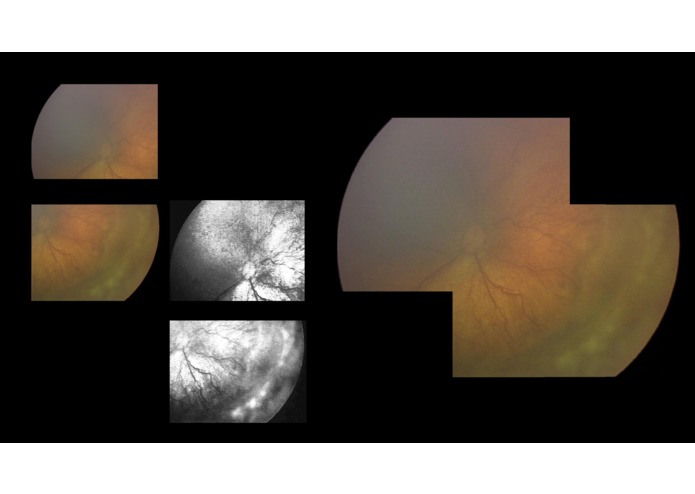

Our project provides a telemedical solution to the remote diagnosis of retinal disease in the absence of an on-site ophthalmologist. Using a low-cost camera, we programmed a complete telemedicine workflow that included camera warping calibration, VLC streaming, image capture to cloud, Dropbox integration, and custom retinal montaging for remote, holistic diagnosis. In addition, we explored the use of Deep Convolutional Neural Networks in classifying retinal images using Tensorflow and the Kaggle Diabetic Retinopathy Dataset.